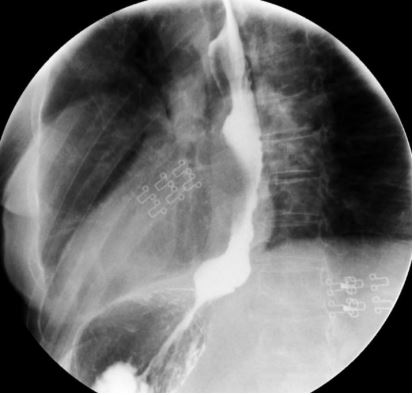

Figure 3: Esophagogastroduodenal transit one year after perforation.

A 67-year-old woman underwent surgery in February 2020 for a giant hiatal hernia containing the entire stomach and part of the transverse colon, with a diaphragmatic hiatus measuring 15x20 cm. CollisNissen fundoplication was performed (EGJ was at the carina level), and the hernial defect was corrected using a 7.5 x 10 cm PTFE (polytetrafluoroethylene) prosthetic mesh without complications at discharge. During outpatient follow-up, the patient reported progressive dysphagia, chest pain, regurgitation, vomiting, and occasional food impaction. A gastroscopy one year post-surgery revealed partial inclusion of the mesh in the esophageal lumen and Collis-Nissen gastroplasty. Initially managed conservatively, a slow mesh inclusion and worsening symptoms led to surgical revision in January 2022. Two perforations were found on the anterior and posterolateral aspects of the neoesophagus formed by the Collis gastroplasty, involving 70% of the circumference. Extrapulmonary mesh, forming an intrathoracic cavity adjacent to the perforation site, was resected. Intraoperative gastroscopy identified the perforation sites, which were sutured, and a Dor-type fundoplication was added, along with a feeding jejunostomy. Postoperatively, the patient experienced dehiscence of the primary perforation repair. Considering the complex situation, the high morbidity associated with esophageal replacement in the infected mediastinal environment, and the elapsed time since the initial problem, and since the leak was well-drained and clinically tolerated, an endoprosthesis was placed. On endoscopy performed on 03/02/2022, a large defect in the esophageal wall covering 70% of the circumference was observed at 34 cm from the dental arch (gastric folds were at 37 cm). A self-expanding metallic WallFlex esophageal prosthesis coated with 105 x 23 mm was placed, anchored proximally with two endoscopic stitches using the OverStich system. The patient was discharged on 18/02/2022 under home hospitalization. The last prosthesis removal on 02/06/2022, after four replacements every four weeks, revealed an elevated mucosal patch replacing the previously described defect. Fluoroscopy confirmed the absence of leakage, and contrast-enhanced oral and intravenous CT showed no complications. The patient resumed a soft diet before hospital discharge. Currently, the patient is asymptomatic from a digestive perspective, with an esophagogastroduodenal transit performed on 27/09/2022 showing no contrast leakage.